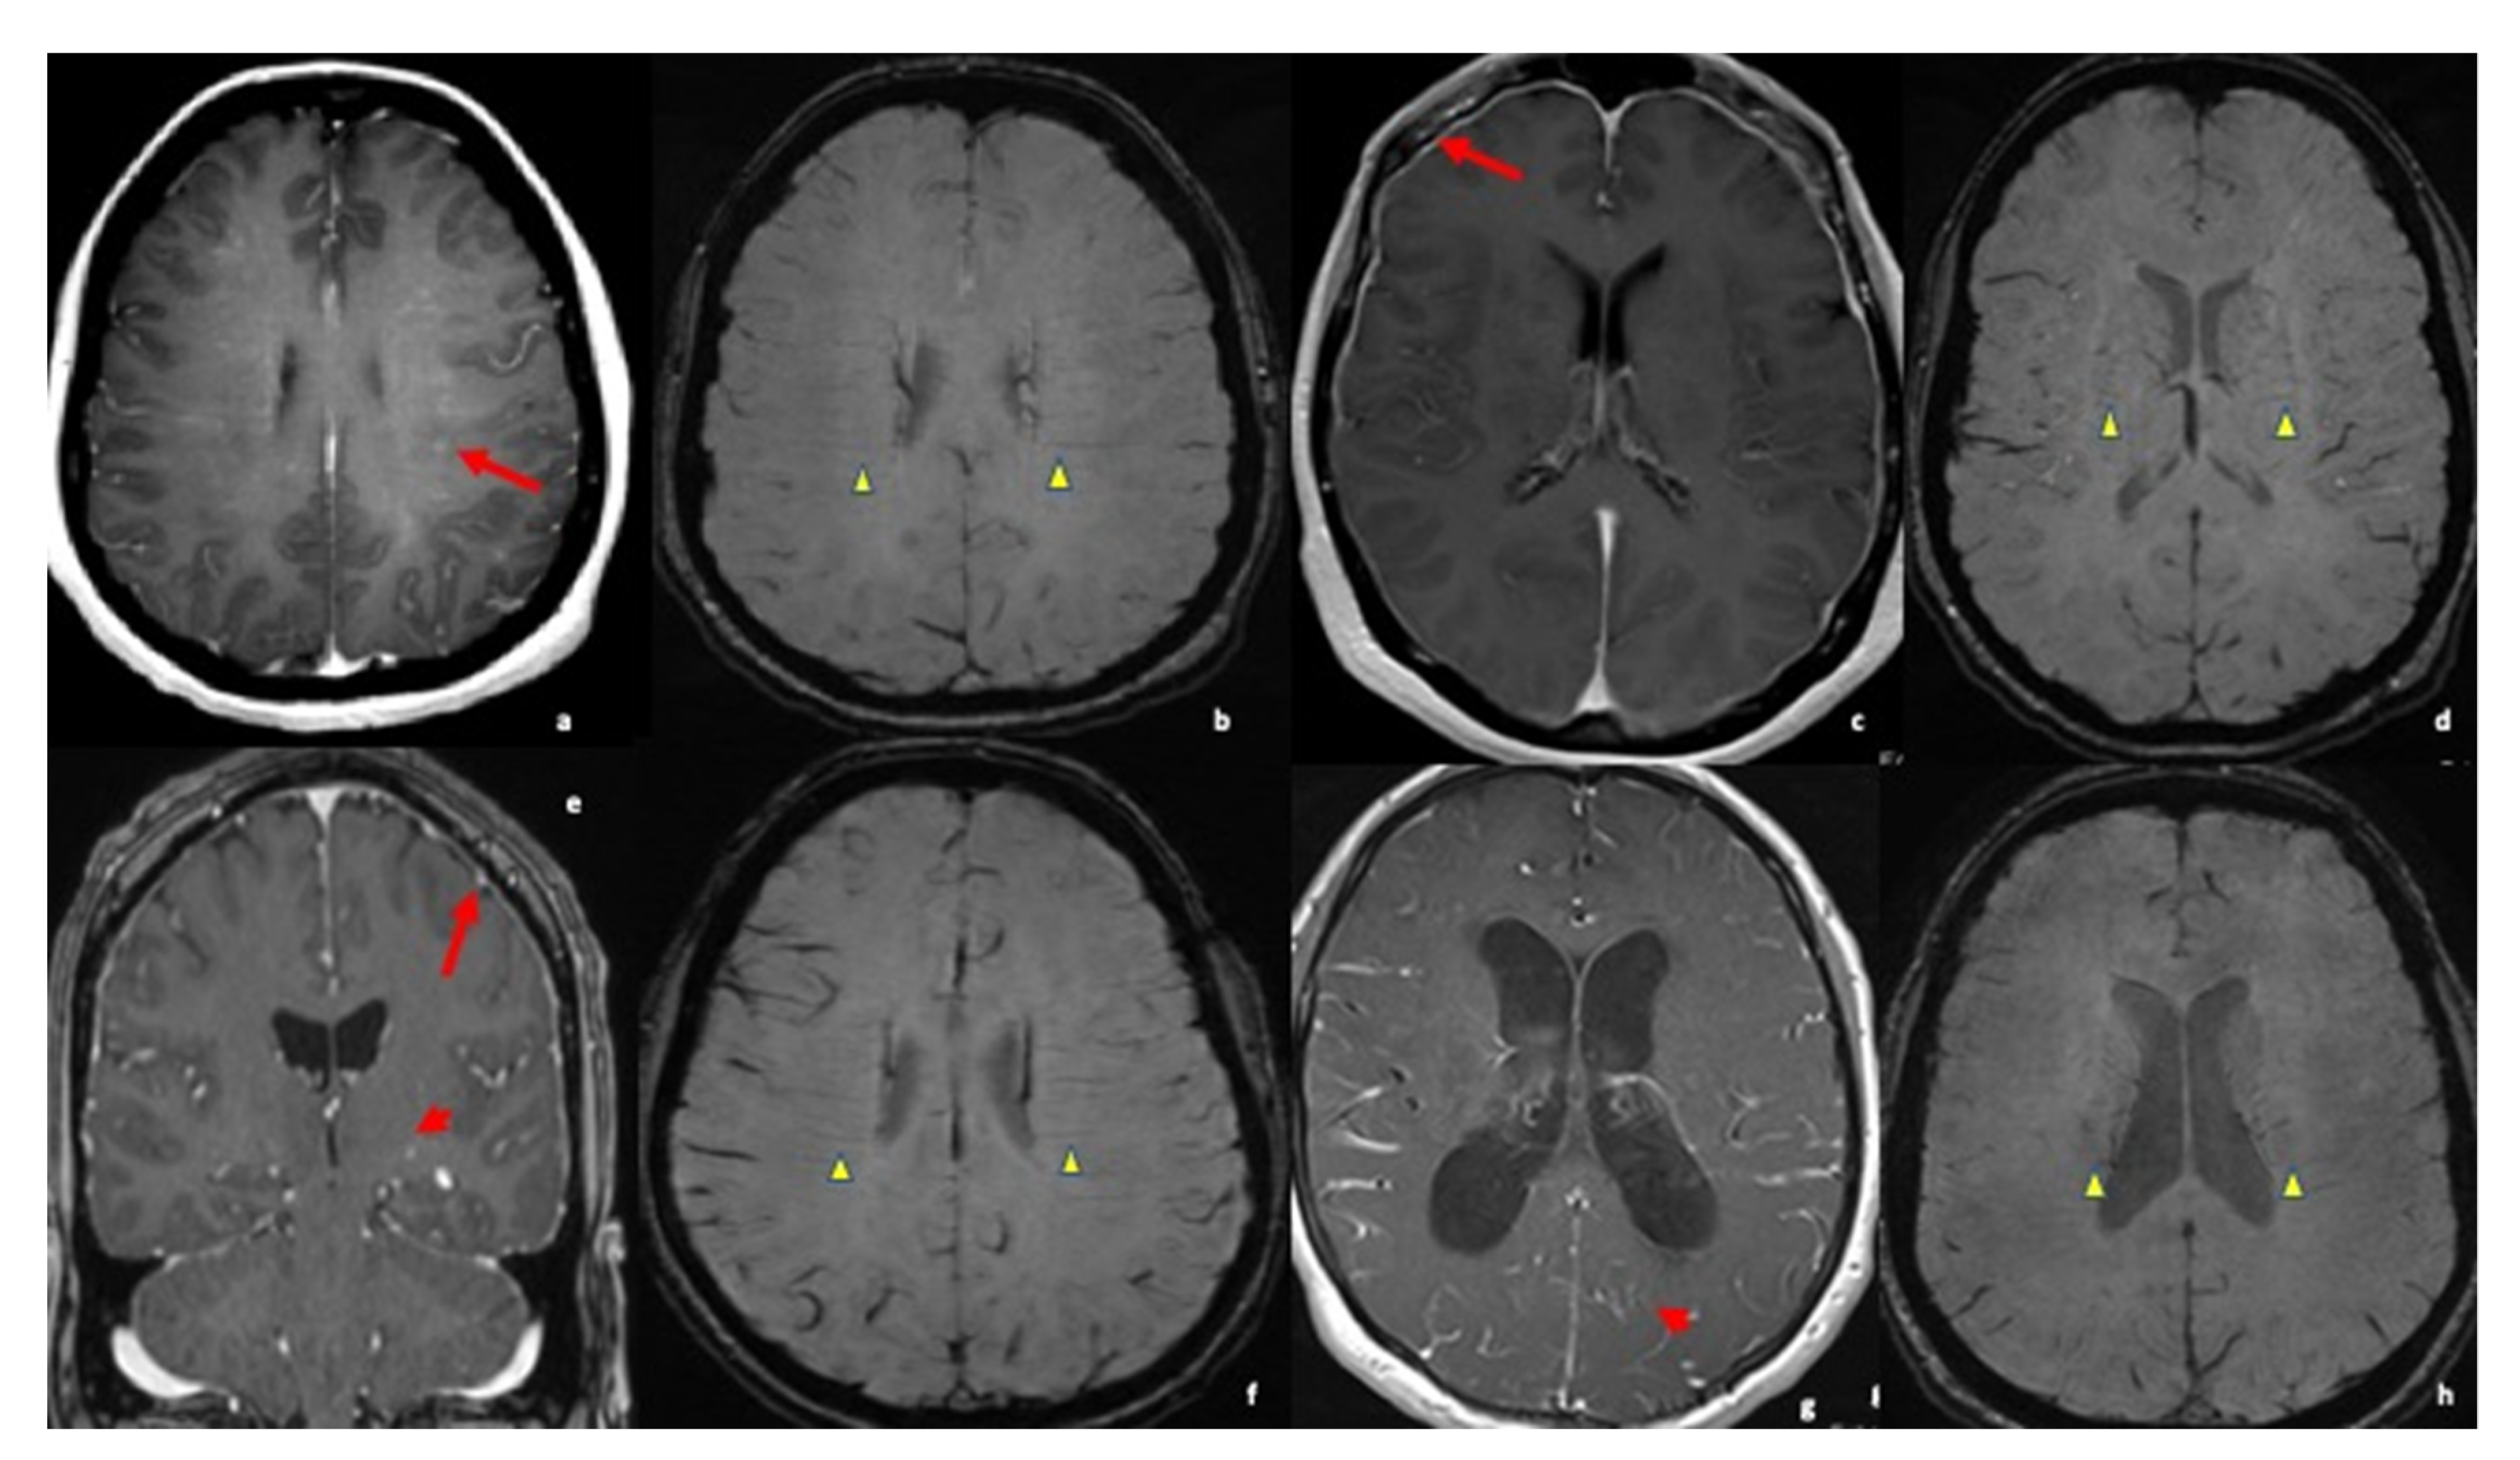

- Zamora, C.; Hung, S.C.; Tomingas, C.; Atkinson, C.; Castillo, M. Engorgement of Deep Medullary Veins in Neurosarcoidosis: A Common-Yet-Underrecognized Cerebrovascular Finding on SWI. AJNR Am. J. Neuroradiol. 2018, 39, 2045–2050. [Google Scholar] [CrossRef]

| 1 * | 56 y.o Female | 2015 | Confusion, thought blocking, leg weakness | WBC: 50 70% lymphocytes; 30% mononuclear Protein: 57 mg/dL | Small focus of restricted diffusion along left lateral medulla Medullary vein sign + | Outpatient follow-up Risk factor reduction | Resolution of acute confusion Residual facial numbness and leg weakness No progression |

| 2 * | 34 y.o. female | 2013 | Intractable headache Weakness Nausea/Vomiting Vision change | CSF ACE: normal Serum ACE: 137 U/L Glucose: 44 mg/dL WBC: 10 Lymphocytes: 79% PMNs: 10% Monos: 7% | Nonspecific markedly abnormal appearance of nodular enhancement and thickening along the pial surface in posterior fossa and basal cisterns and along tentorium and interhemispheric fissure. Developing hydrocephalus Medullary Vein sign + | IV solumedrol 1 g for 3 days Followed by 40 mg prednisone PO Methotrexate 10 mg weekly VP Shunt | No show to several appts. Headaches/vomiting unresolved but vision problems improved |

| 3 * | 62 y.o. Female | 2015 | Double vision, facial paresthesia, proprioception/balance deficits | CSF ACE: normal CSF Glucose: 59 mg/dL Protein: 41 mg/dL WBC: 5 | Diffuses dural thickening with marked dural enhancement in parasellar region Medullary vein sign + Mild leptomeningeal enhancement of optic nerves | 1000 solumedrol for four days, followed by PO steroid 60 mg for one month Methotrexate Rituximab Q6 months | Continued headaches after cessation of steroids. Visual problems after cessation of steroids. Was restarted on a steroid taper. Subsequently weaned off steroids and started on Methotrexate in 2017, which improved headaches and visual symptoms |

| 4 * | 32 y.o. female | 2018 | Intermittent monocular blindness and blurry vision Headache Vertigo N/V Numbness | CSF protein: 66 mg/dL CSF Glucose: 54 mg/dL WBC: 6 35% neutrophil 48% lymphs | Scattered nonenhancing parenchymal lesions in white matter of cerebral hemispheres Medullary vein sign + | 1 g Solumedrol IV TI, transitioned to PO prednisone taper 1 dose IV methotrexate transitioned to 25 mg oral once per 1 week | Improvement in N/V, headaches, and vertigo. Still some residual vision impairment treated with subcutaneous methotrexate per her ophthalmologist |

| 5 * | 33 y.o. Female | 2018 | Papilledema Neck pain New blurry vision headaches | Protein: 216 mg/dL Glucose: 38 mg/dL WBC: 7 neutrophil % 1 Lymphocyte % 70 Monocytes % 27 ACE CSF: 3.5 | Scattered bilateral cerebral white matter lesions, some with associated enhancement. Leptomeningeal enhancement Medullary Vein sign + | Prednisone taper transition to imuran | Complete resolution of symptoms |